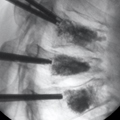

Percutaneous Vertebroplasty (PVP) או Vertebroplasty Vertebroplasty (PKP)

עמוד השדרה הוא אחד האתרים השכיחים לגרורות בעצמות של גידולים ממאירים, וגרורות בגוף החוליה שכיחות יותר. הרס עצם הנגרם על ידי גידולים גרורתיים מוביל לעיתים קרובות להתמוטטות חוליות או לעיוות, דחיסת חוט השדרה, שברים פתולוגיים, היפוקלצמיה והיפרפראתירואידיזם משני, הגורם לכאבים קשים ותפקוד לקוי, המשפיעים בצורה רצינית על איכות החיים של החולים, כדי לקצר את משך החיים.

טיפול סימפטומטי קונבנציונלי כולל משככי כאבים בפה, הקרנות פליאטיביות, ניתוחים וטיפול סיסטמי כגון ביספוספונטים. מטופלים רבים נאבקים בטיפולים אלו עקב ביקורים חוזרים, יעילות ירודה ותופעות לוואי. בשנת 1984, המנתח הצרפתי Galibert דיווח על יישום הזרקת מלט עצם דרך עורית בטיפול בכאב בלתי פתיר הנגרם על ידי המנגיומה השנייה של עמוד השדרה הצווארי, ויצר תקדים להזרקת מלט עצם עורית זעיר פולשנית בטיפול בנגעים בחוליות. תוך 48 שעות לאחר ניתוח ורטרופלסטיה מלעורית (PVP) או קיפופלסטיקה בלון מלעורית (PKP), הקלה משמעותית בכאב הייתה קשורה להפחתת השימוש בתרופות ולשיפור הפרמטרים התפקודיים.